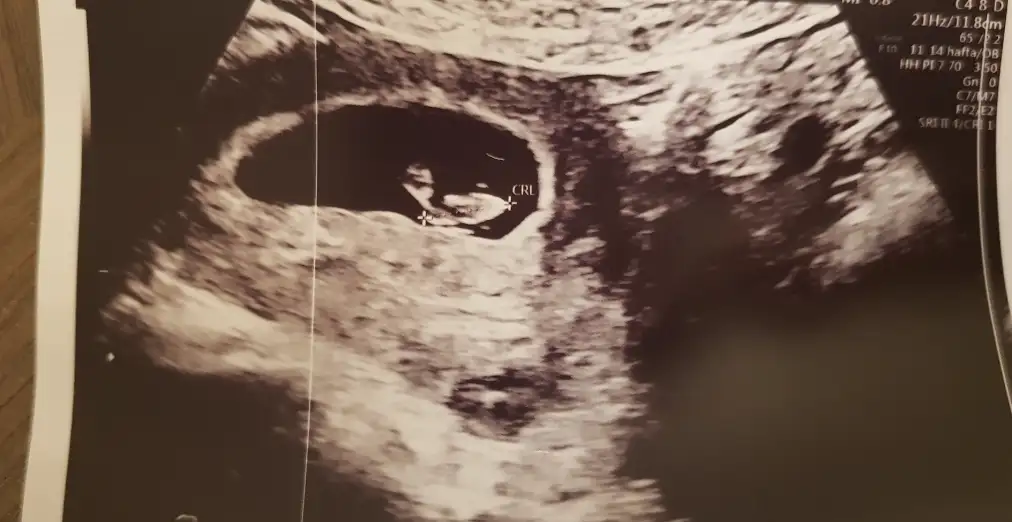

dr soylemeden siz gorun genital nub teorisi ( bebegin cinsiyeti)

Ikra meyra Ikra meyra muayneden çıktım koştura koştura sana geldim çok merak ediyorum 1 hafta sonraki usg 8 haftalık ama gelişim 7 haftaymış yine yorumlar mısın 🤗

6-7 haftalık gebelikte bebek plasentaya çok yakın konumdadır ve elinizdeki vajinal görüntüde bebek sağdaysa erkek. Bu yöntem %97 doğrudur yazıyor sitede